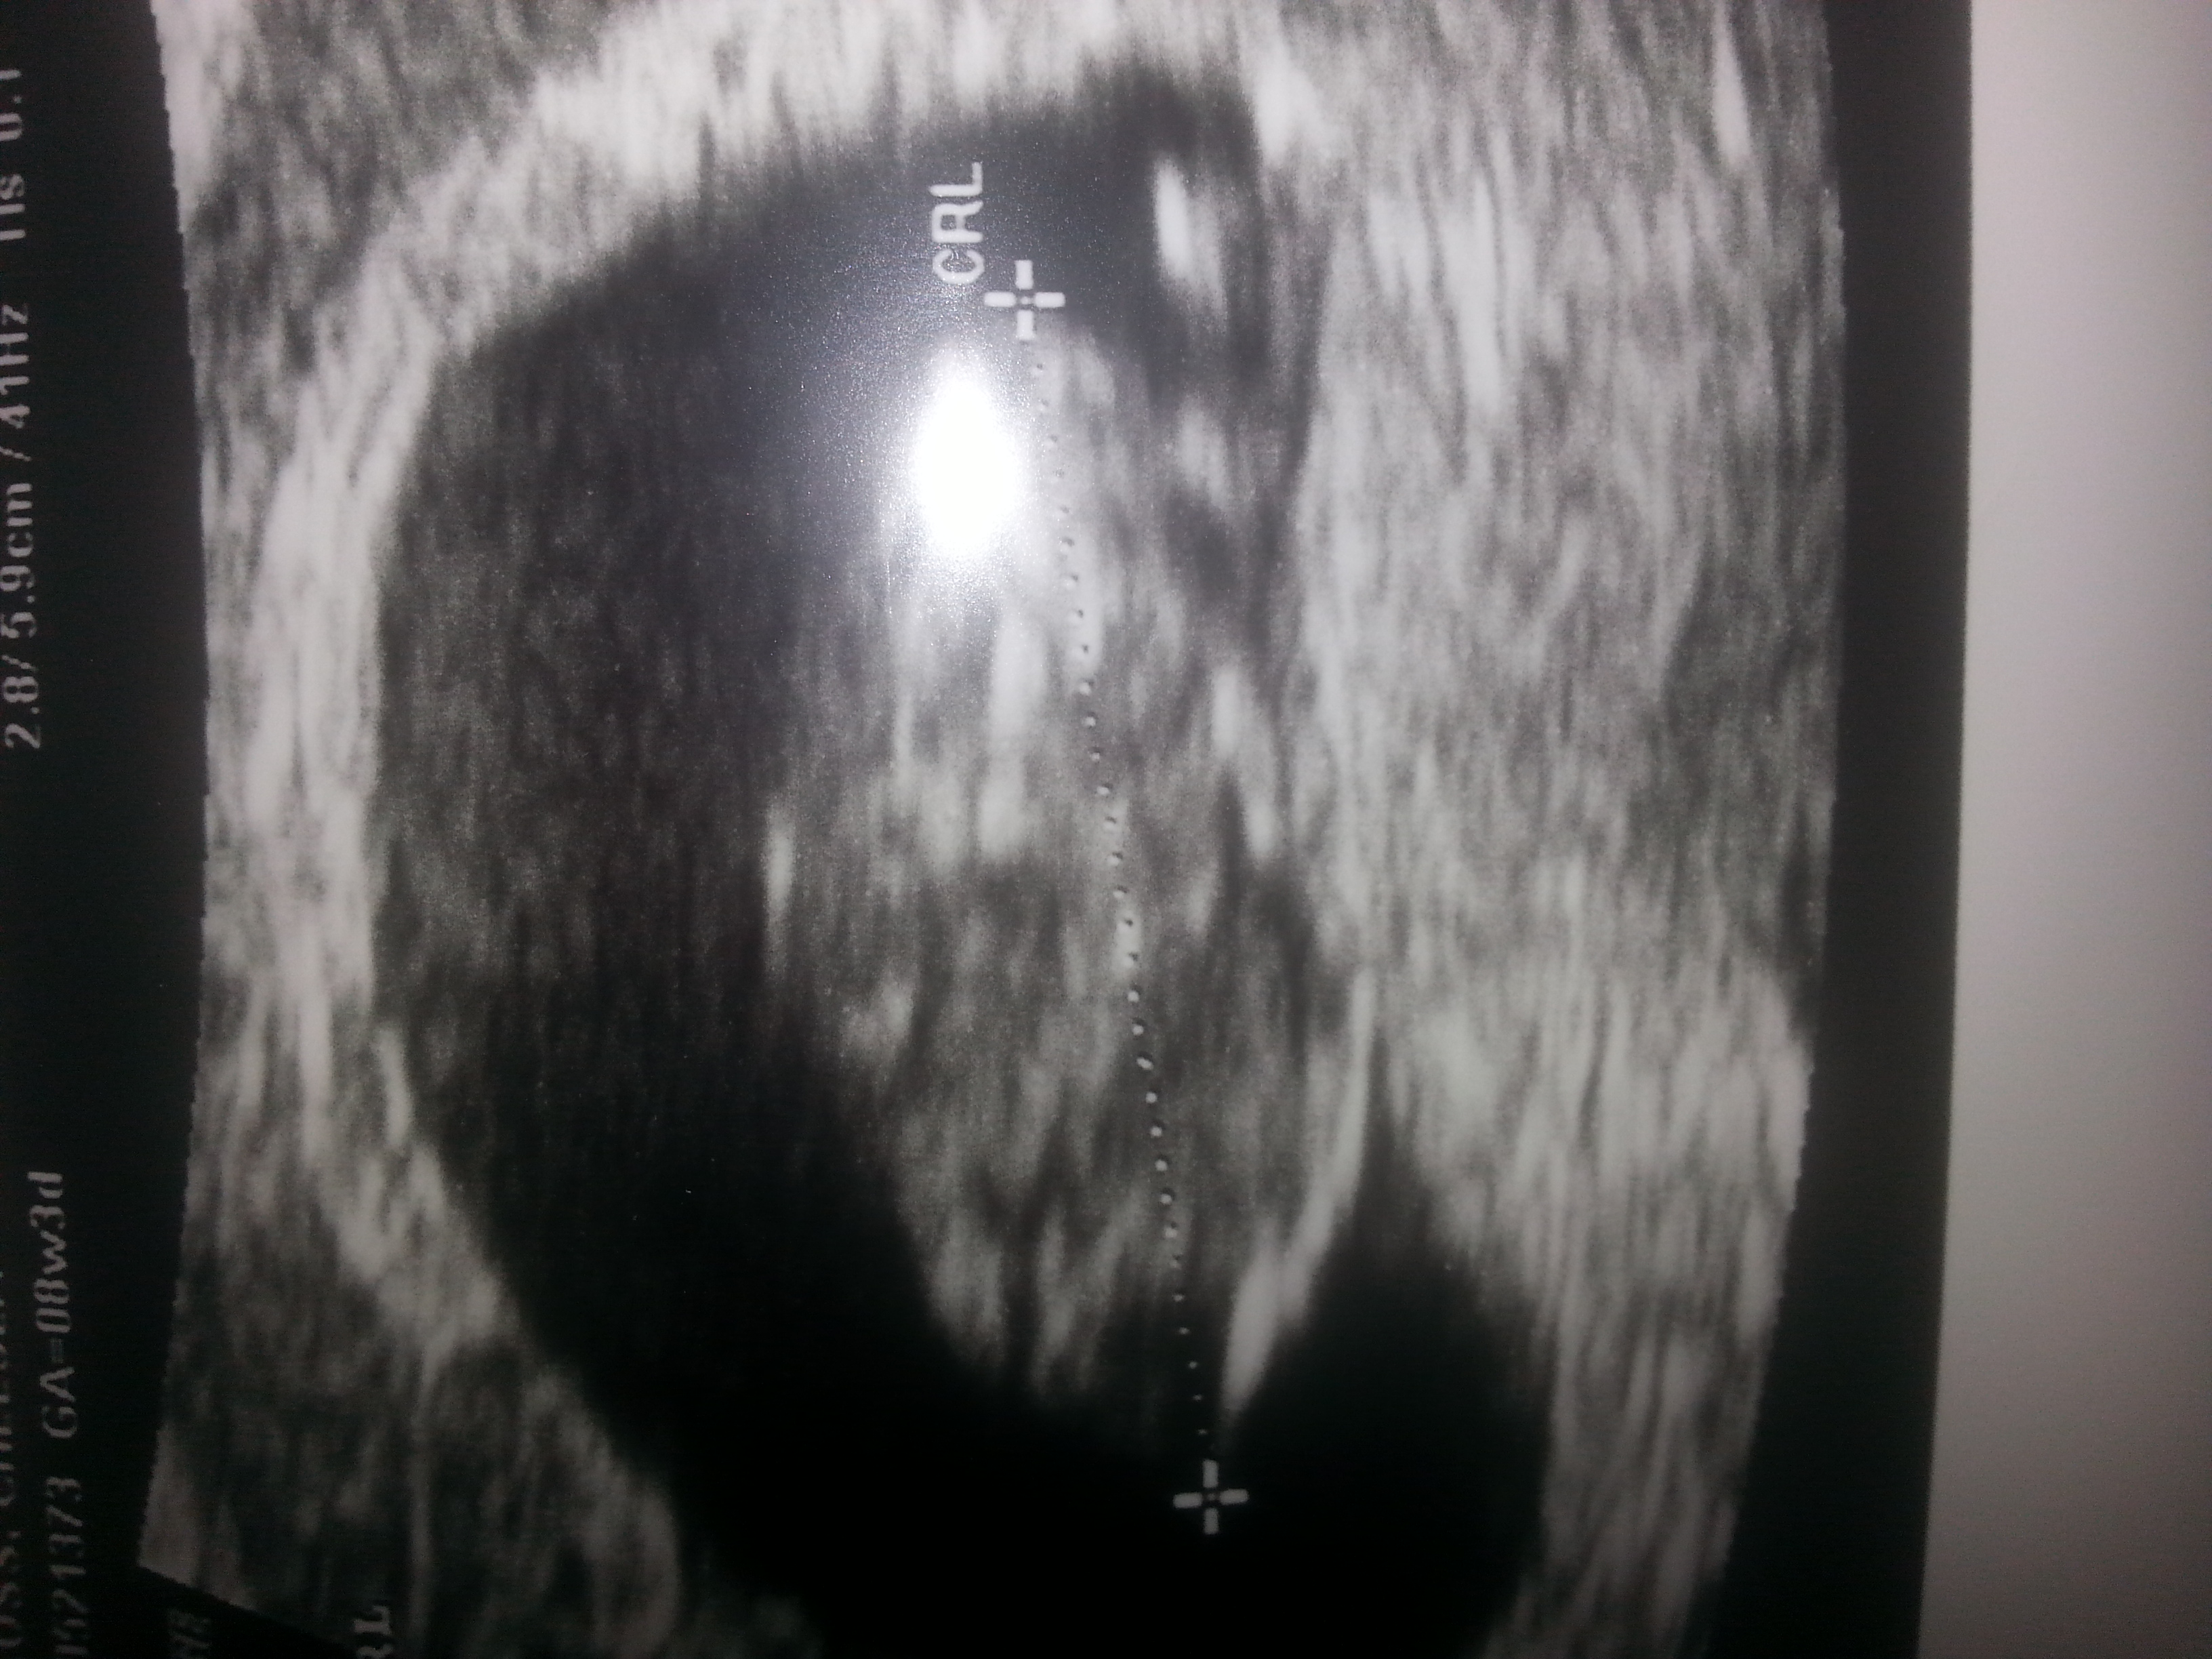

Hi everyone im currently 19 weeks pregnant and find out in 4 days what im having. Im guessinga baby girl but not sure. So any of you have any guesses?Attachment 22856Attachment 22857Attachment 22858